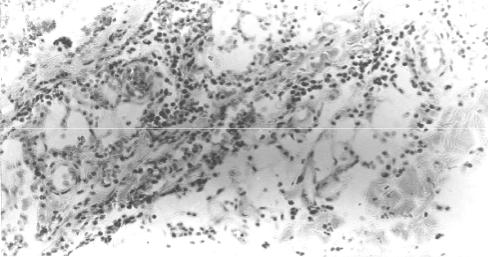

Рис. 18. Репаративная регенерация в ранах (окраска гематоксилином и эо- зином): а организация некроза в ране после первичной хирургической обра- ботки с ее заживлением первичным натяжением, 7-е сутки (× 100); б началь- ные признаки образования грануляционной ткани в жировой клетчатке под де- маркационным лейкоцитарным валом при развитии нагноения раны, 7-е сутки (× 100); в сформированная грануляционная ткань отграничивает зону гной- ного расплавления некротизированных тканей при заживлении раны вторич- ным натяжением, 25-е сутки (× 75)